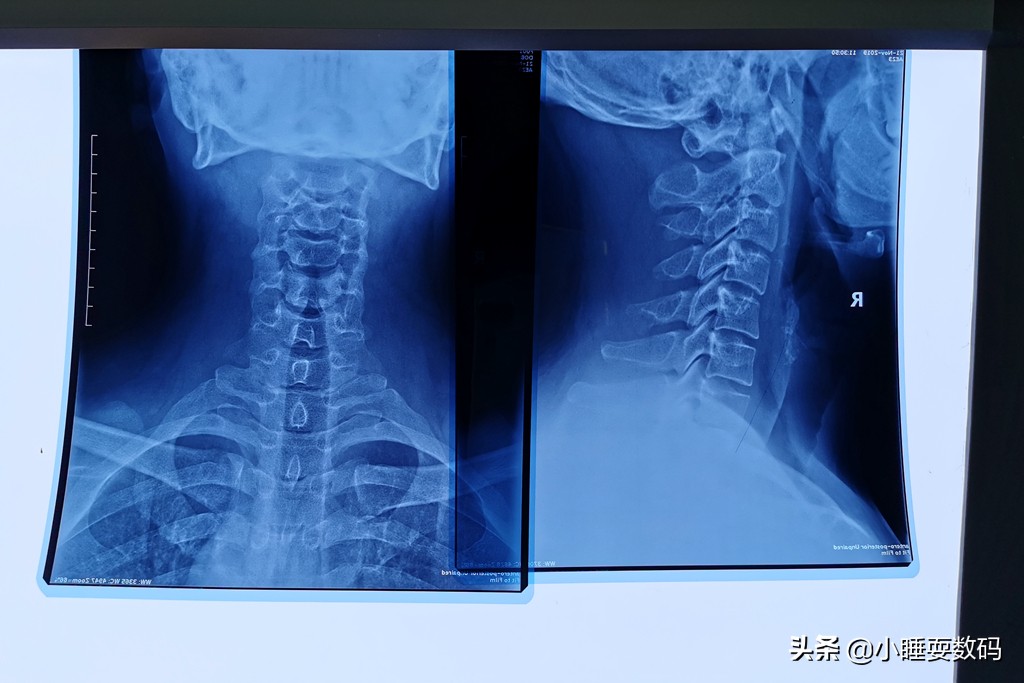

小睡本人也是一名颈椎病患者,工作上需要长期面对电脑,加上自己没有注意保养,久而久之也发展成了颈椎病。前几天甚至出现了头晕、乏力的症状,到医院拍了CT片子检查,颈椎的生理弧度几乎完全消失了,从上面的图片可以明显的看到。从医院开了药、买了牵引矫正器材,医生还叮嘱说睡觉不要枕太高的枕头睡觉,这是为什么呢?因为枕太高的枕头,脖子的姿势就相当于白天低头看手机。

再测评之前还是要普及一下,到底什么才是对颈椎好的枕头?我们都知道人体正常的颈椎应该是有一个向前的弧度,像弯弯的香蕉一样,可以增加颈椎弹性,保护头部。但如果睡觉枕的枕头太高,仰睡的时候效果就像我们白天玩手机低头一样,慢慢的颈椎就会变直。同样枕头太低的话,我们侧睡时,头部就会失去支撑,肩膀受压颈椎侧弯……因此颈椎病的形成和枕头的高低、睡觉的姿势都有关系,通过上面两幅图大家可以直观的感受到。